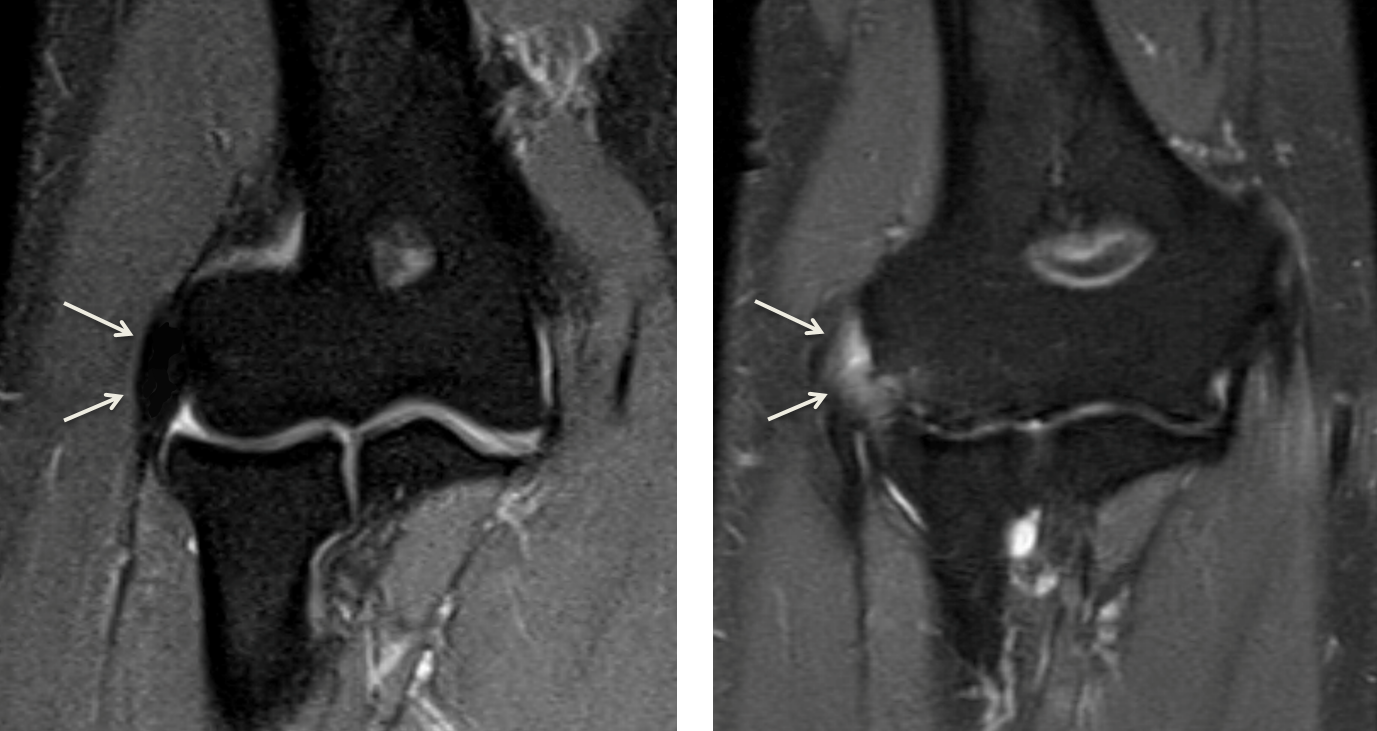

From radiologykey.com

Elbow Epicondylitis Radiology Key What Is Elbow Lateral Epicondylitis Tennis elbow, or lateral epicondylitis, is a condition in which the forearm muscles become damaged from overuse. Tennis elbow, or lateral epicondylitis, is typically caused by the same motion as a tennis downstroke. Lateral epicondylitis, also commonly referred to as tennis elbow, describes an overuse injury that occurs secondary to an eccentric overload of the common extensor tendon at. Tennis. What Is Elbow Lateral Epicondylitis.